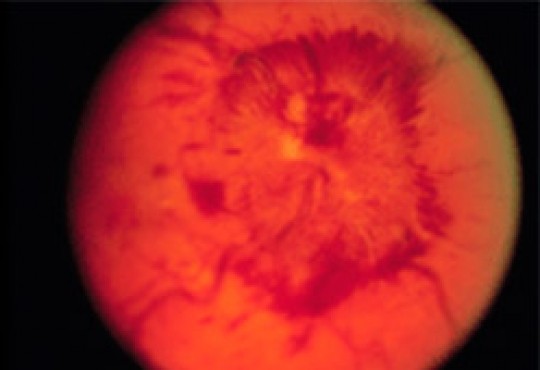

El nervio óptico se ve como un órgano redondeado, plano, de bordes netos. Cuando hay edema de papila los

bordes se ven borrosos y sobreelevados. Se suelen ver hemorragias y en ocasiones exudados, que son puntos

blancos (ver figura).